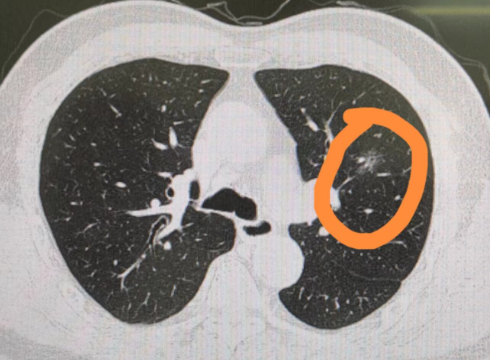

肺部磨玻璃结节,是肺部磨砂玻璃密度一样的圆形、类圆形的云雾状病灶,大小不超过3厘米。根据密度高低,它可以分为纯磨玻璃结节与混合磨玻璃结节。

尽管炎症、结核、真菌感染、肺泡出血等引起肺泡腔充气程度改变的疾病,都可以表现为磨玻璃结节,但长期存在的磨玻璃结节有发展为肺癌的风险,因此需要引起大家的重视。

肺部磨玻璃结节肿瘤性病变可分为四个病理阶段:不典型腺瘤样增生、原位腺癌、微浸润腺癌和浸润腺癌。前两者可以列为良性阶段,后两个被列为恶性阶段。这四个阶段被认为是危险程度逐渐升高、连续性、渐进式的生长过程,且彼此相邻阶段有时候很难区分。肿瘤性的磨玻璃结节多数属于惰性肿瘤,生长缓慢,转移概率低。